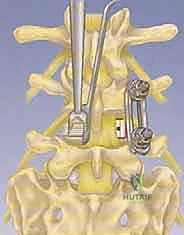

تقنية PLIF (الاندماج الفقري القطني الخلفي)

في هذه التقنية، يتم الوصول إلى العمود الفقري من الخلف مباشرة. يقوم الجراح بإزالة جزء من العظم (الصفيحة الفقرية Laminectomy) للوصول إلى القناة الشوكية. يتم سحب الأعصاب برفق إلى الجانبين للوصول إلى القرص التالف وإزالته، ثم يتم إدخال "أقفاص" (Cages) مدعومة بطعوم عظمية من كلا الجانبين.

* الميزة: تتيح رؤية ممتازة للقناة الشوكية وإزالة شاملة للضغط من الجانبين.

الخطوة 4: زراعة القفص والطعم العظمي (Cage Insertion)

يتم إدخال قفص مصنوع من مادة PEEK أو التيتانيوم، مملوء بطعم عظمي (يؤخذ غالباً من المريض نفسه أو طعم صناعي)، في المساحة الفارغة. هذا القفص يعيد الارتفاع الطبيعي للفقرات ويخفف الضغط عن منافذ الأعصاب.